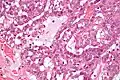

Polymorphous low-grade adenocarcinoma. H&E stain. Micrograph of a polymorphous low-grade adenocarcinoma. H&E stain.

Micrograph of a polymorphous low-grade adenocarcinoma. H&E stain.